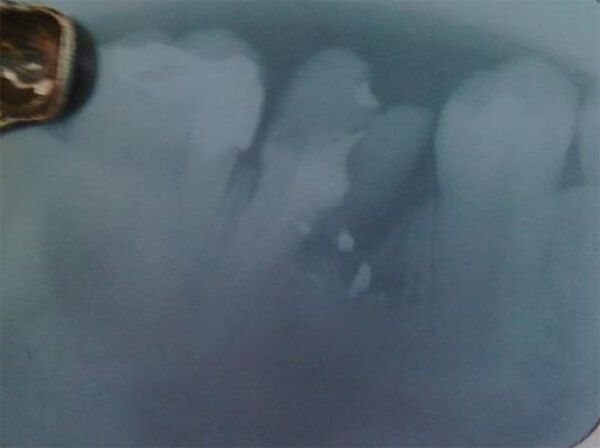

La exploración de conductos con limas Hedstroem informó radiográficamente: a) destrucción parcial del piso de la cámara pulpar; b) rarefacción ósea periapical, ovalada, de aproximadamente 8mm de diámetro, con límites poco definidos e irregulares que compromete la raíz mesial; c) línea radiopaca en ápice distal no concluyente para diagnóstico (señalada en la figura) d) conductometría en raíz distal Rx= 21mm, Real= 22mm (Figura 2).

Figura 2. Exploración de conductos radiculares.

Se planteó el diagnóstico presuntivo de granuloma periapical en 46.